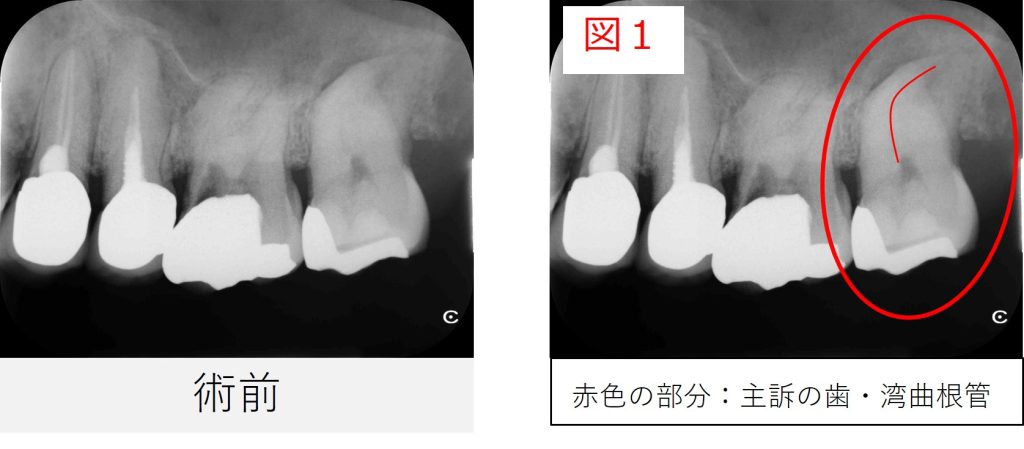

●レントゲン・CT画像所見

レントゲンおよびCT画像では、左上7番の根尖部に黒い影(骨のない部分)を認め、炎症が上顎洞(鼻と繋がっている空洞)にまで及んでいる所見が確認されました。

また、根管は強く湾曲しており、治療の難易度が高い症例でした。

根管が大きく曲がっている場合、器具を根の先まで安全に通すことが難しく、

わずかな操作ミスで器具が折れてしまったり、根の壁を傷つけて穿孔(せんこう:穴が開いてしまう)するリスクがあります。